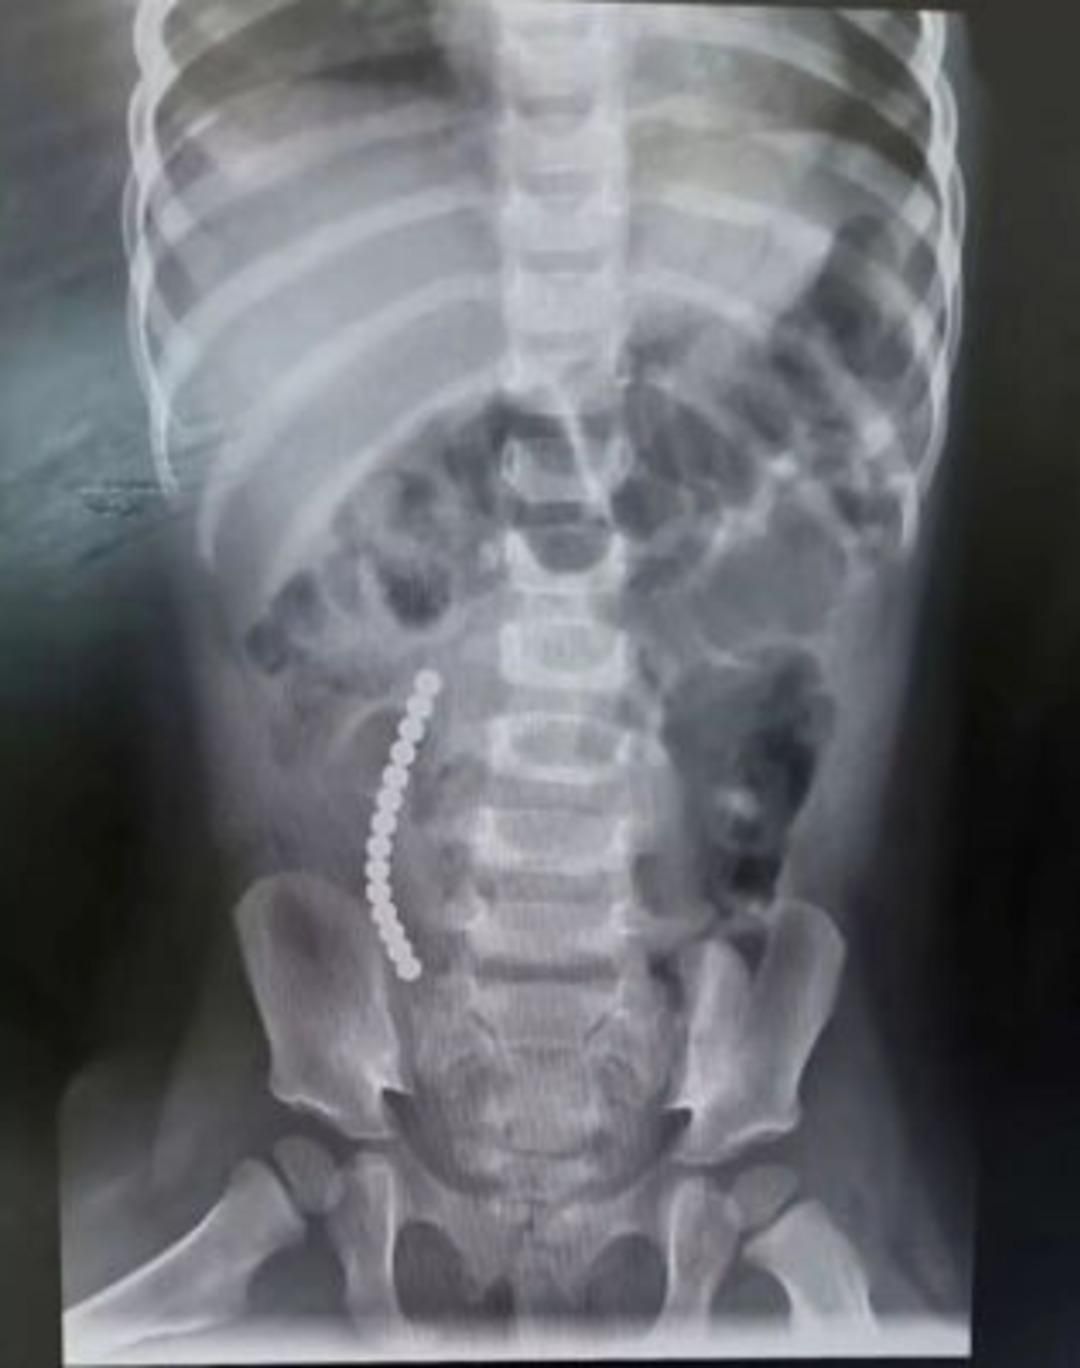

14 tane yuttu, doktorlar görünce şaştı kaldı

İngiltere’nin Basildon kentinde yaşanan olay dehşete düşürdü. İki yaşındaki Rebecca McCarthy’nin annesi Sam, çocuğunun kusmaya başlamasıyla bir şeylerin ters gittiğini fark etti. Hastaneye kaldırılan çocuğun 14 adet mıknatıs yuttuğu ortaya çıktı.

BAĞIRSAKLARI ÇIKARTILDI

The Mirror’ın haberine göre ameliyata alınan çocuğun operasyon sırasında bağırsakları dışarı çıkartıldı. Ameliyattan sonra bir dizi sağlık problemi yaşayan küçük çocuğun annesi, internetten satın alınan oyuncakların tehlikelerini vurgulayarak, ”Bizim yaşadıklarımızı kimsenin yaşamasını istemem, bu kaza ailemizi perişan etti” ifadelerinde bulundu. McCarthy’nin hastanedeki tedavisi sürüyor.